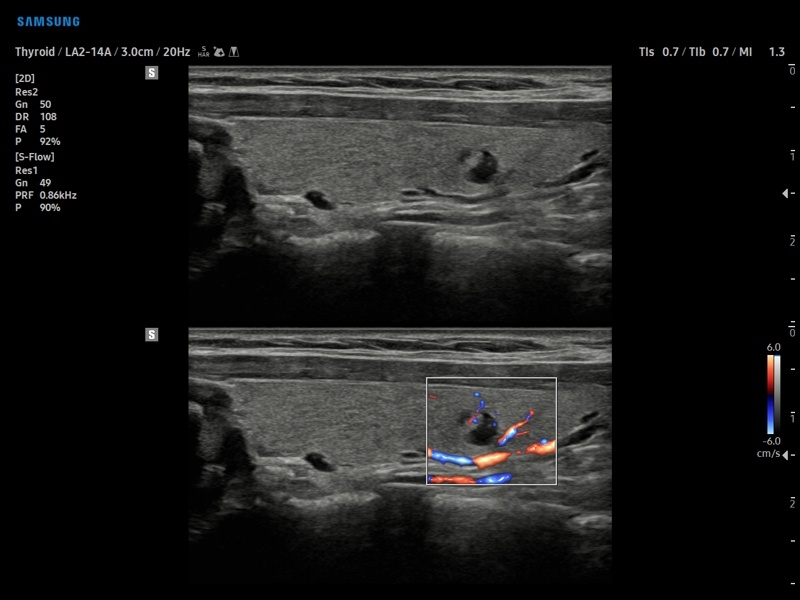

• S-Detect для исследования молочной железы и щитовидной железы

• МодульS-Detect Breast- программа автоматического обнаружения и анализа образований молочной железы у женщин, измерение и классификация по системе BI-RADS.

• МодульS-Detect Thyroid- программа автоматического обнаружения образований и анализа щитовидной железы, измерение и классификация по системе системе TI-RADS.

• Модуль S-Detect Breast - программа автоматического обнаружения и анализа образований молочной железы у женщин, измерение и классификация по системе BI-RADS.

• Модуль S-Detect Thyroid - программа автоматического обнаружения образований и анализа щитовидной железы, измерение и классификация по системе системе TI-RADS.